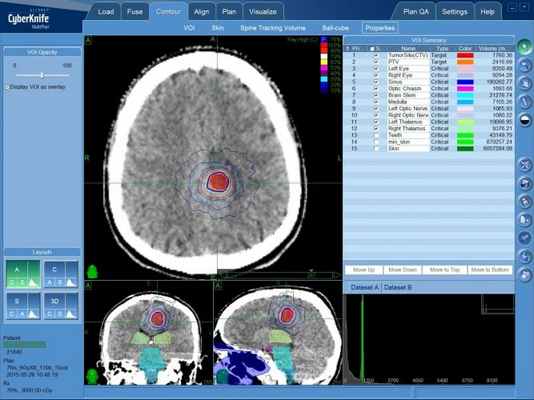

Лечение на системе КиберНож

Для группы опухолей головного мозга, которые объединяют в группу “астроцитома” радиохирургическое лечение на КиберНоже имеет крайне избирательное применение. Как правило, астроцитома (является разновидностью глиомы, глиальной опухоли) диагностируется после того, как опухоль проросла в соседствующие структуры мозга и вызвала неврологические симптомы из-за нарушения нормальной работы головного мозга.

Безоперационное лечение астроцитомы — КиберНожом. Зона, выделенная красным, соответствует объему опухоли, в который будет подана высокая доза излучения

В таком случае объем опухоли уже превышает максимальный рекомендованный для лечения на КиберНоже. Именно поэтому лечение астроцитомы всех видов (пилоцитарная астроцитома, фибриллярная астроцитома, анапластическая астроцитома и глиобластома) обычно начинается с хирургического удаления максимально возможного объема опухоли и поврежденных тканей головного мозга с последующим облучением ложа опухоли.

В случае, если объем ложа опухоли (места соприкосновения сохраненных тканей головного мозга и удаленных в результате нейрохирургической операции тканей не превышает рекомендованных значений, то проводится радиохирургическое лечение этой области на КиберНоже.

Однако, если опухоль неоперабельна ввиду состояния пациента, глубокого залегания вблизи критических зон или ее нахождения в функционально важных отделах головного мозга, пациенту может быть назначено сочетанное лечение, включающее лучевую терапию на линейном ускорителе и радиохирургию на КиберНоже.